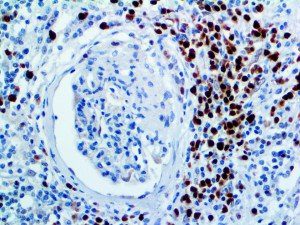

It is the ICU physician who is most likely to witness one of the deadliest manifestations of the abnormal immunological response, the cytokine storm syndrome (CSS). This response is also referred to by some as the cytokine release syndrome (CRS). CSS is characterized by continuous activation and expansion of macrophage and lymphocyte populations, which secrete large amounts of cytokines, causing the cytokine storm. This massive cytokine release is akin to hemophagocytic lymphohistiocytosis (HLH) disease, a syndrome characterized by initial unchecked and persistent activation of cytotoxic T lymphocytes and NK cells.

Clinical and laboratory manifestations of HLH include fever, enlarged liver and/or spleen, neurologic dysfunction, coagulopathy, liver dysfunction, cytopenias (i.e., low levels of erythrocytes, leukocytes, and/or platelets), hypertriglyceridemia, hyperferritinemia, hemophagocytosis, and eventually diminished NK cell activity as the immune system becomes progressively paralyzed. HLH can be familial (primary HLH) or secondary to another disease process (sHLH), such as rheumatic disease, in which it is referred to as macrophage activation syndrome (MAS, characterized by elevated ferritin).